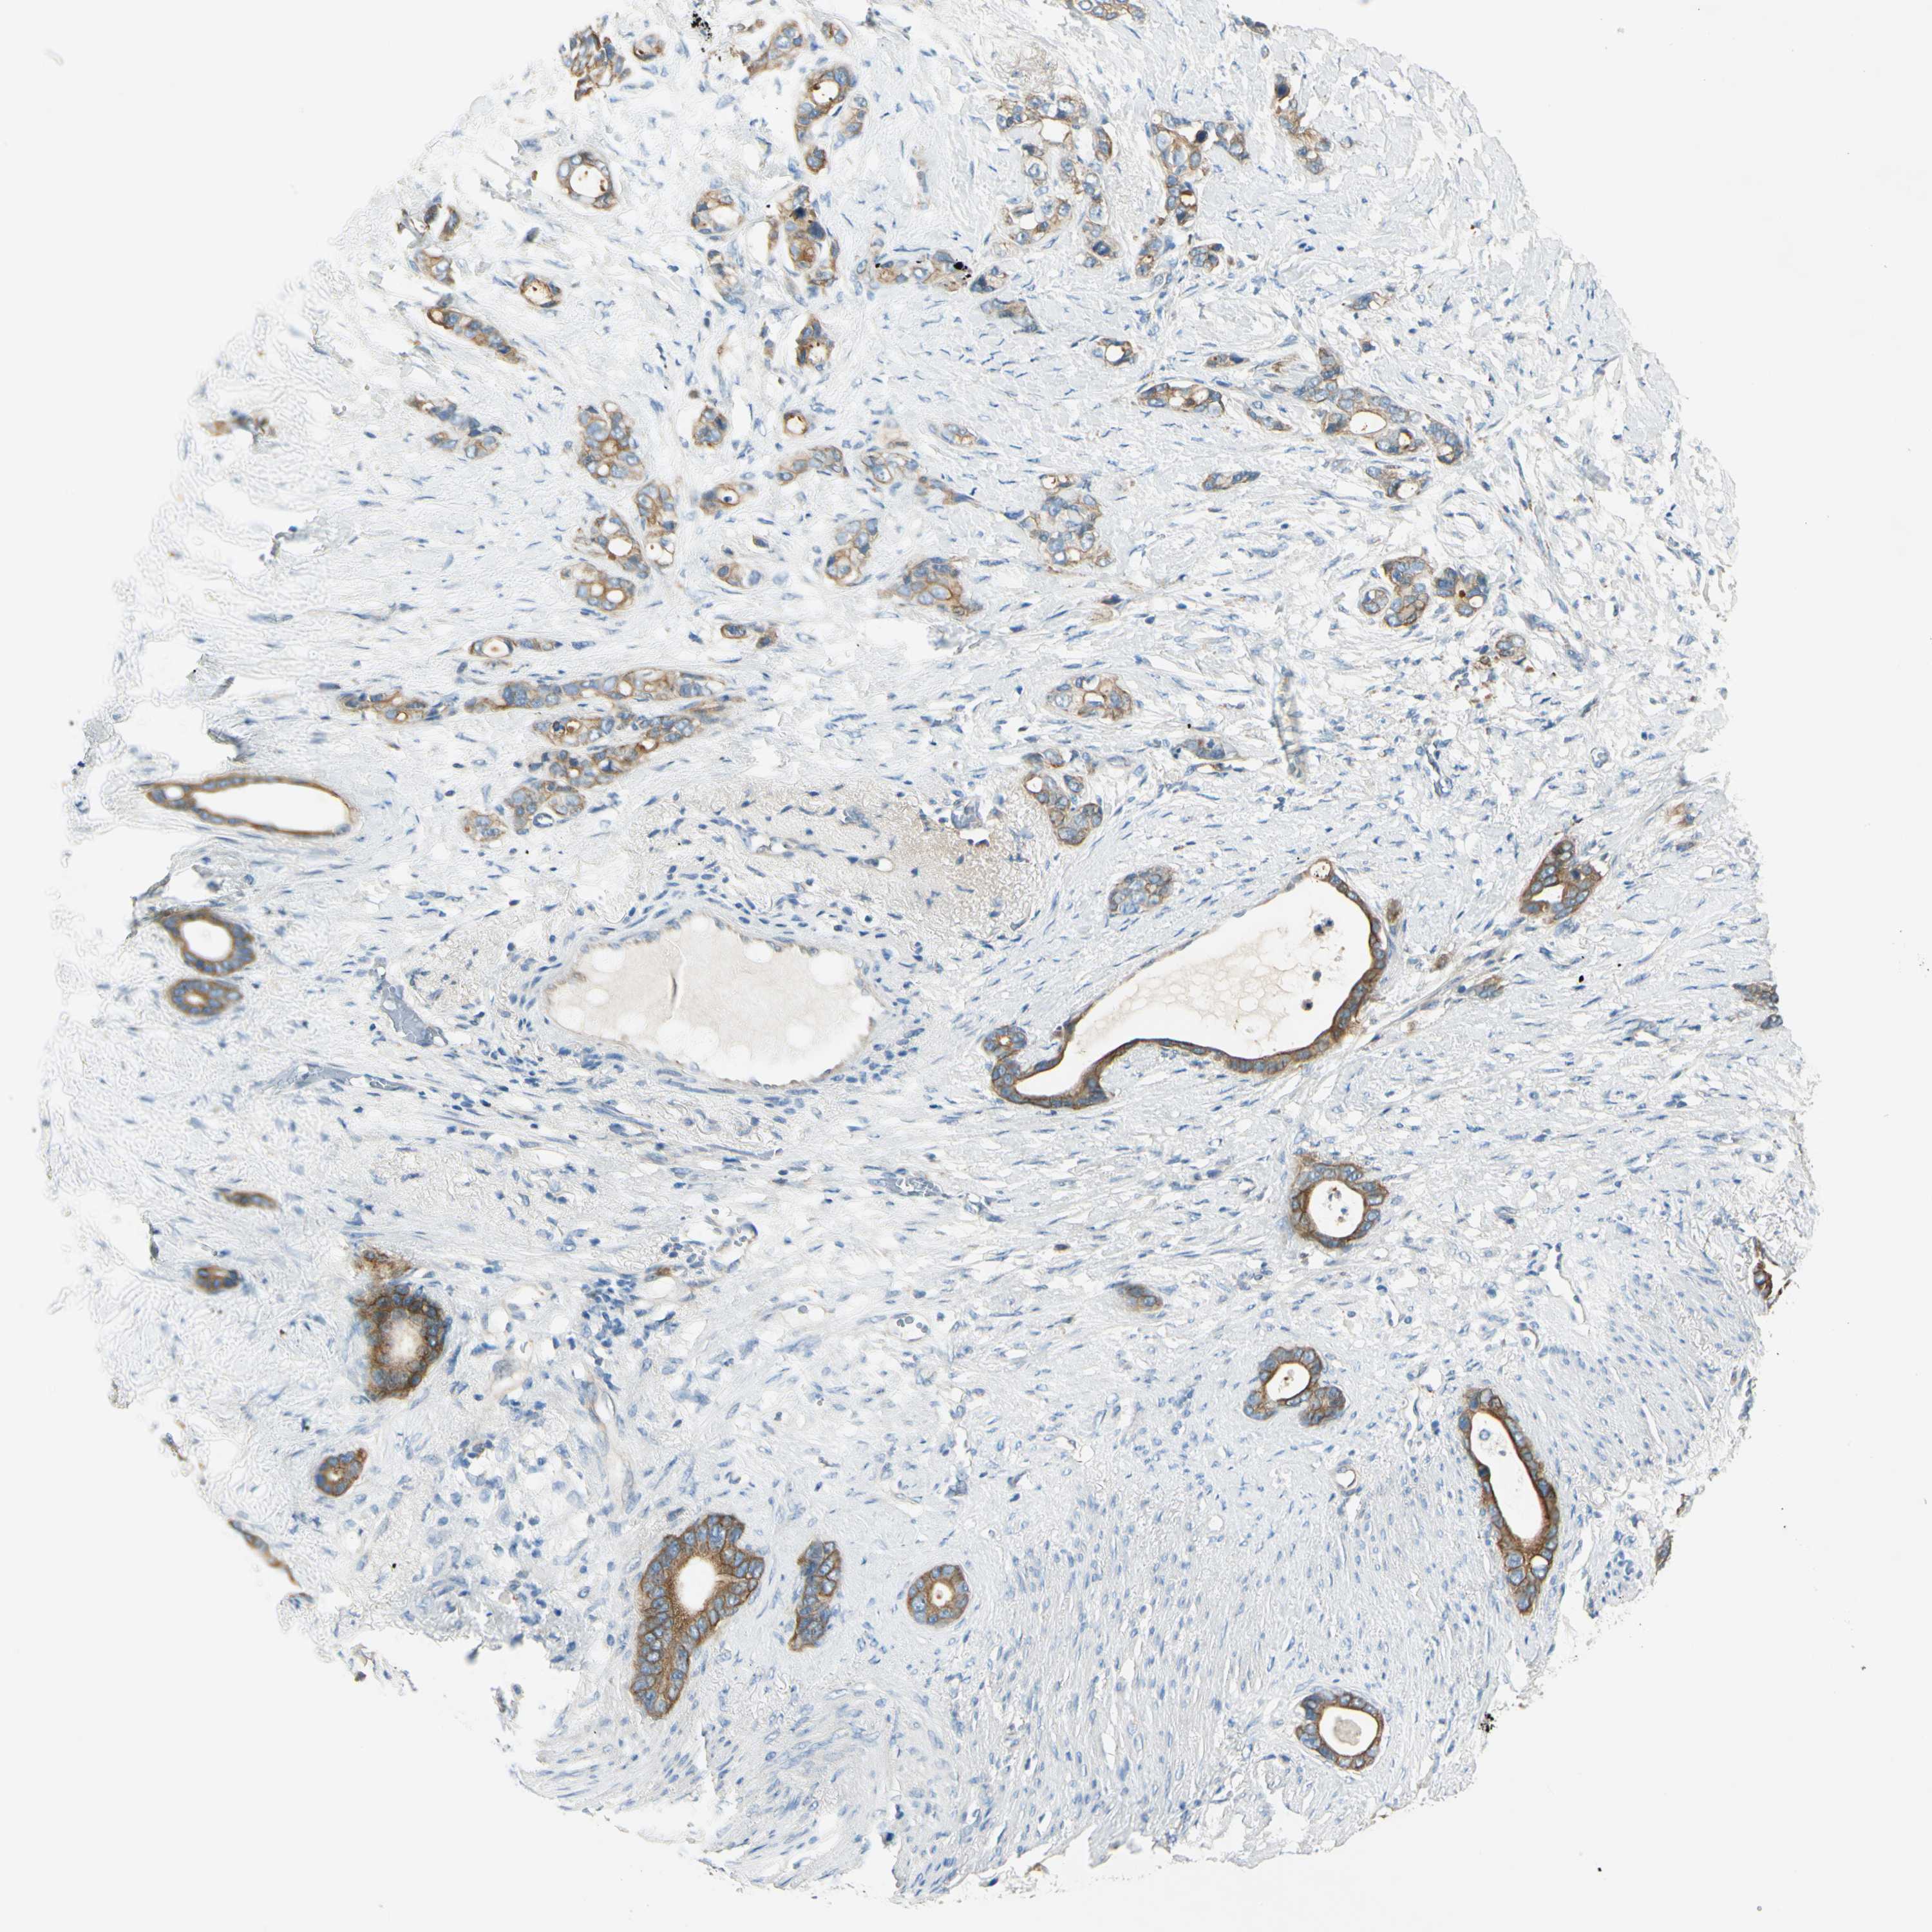

STOMACH CANCER - Protein expressioni

A mouse-over function shows sample information and annotation data. Click on an image to view it in a full screen mode. Samples can be filtered based on level of antibody staining by selecting one or several of the following categories: high, medium, low and not detected. The assay and annotation is described here.

Note that samples used for immunohistochemistry by the Human Protein Atlas do not correspond to samples in the TCGA dataset.

Antibody stainingi

Antibody staining in the annotated cell types in the current human tissue is reported as not detected, low, medium, or high, based on conventional immunohistochemistry profiling in selected tissues. This score is based on the combination of the staining intensity and fraction of stained cells.

Each image is clickable and will lead to virtual microscopy that enables deeper exploration of all samples and also displays staining intensity scores, fraction scores and subcellular localization as well as patient and tissue information for each sample.

Antibody HPA009309

Antibody CAB010757

Staining

High

Medium

Low

Not detected

Intensity

Strong

Moderate

Weak

Negative

Quantity

>75%

75%-25%

<25%

None

Location

Nuclear

Cytoplasmic/membranous

Cytoplasmic/membranous,nuclear

Adenocarcinoma, NOS

Adenocarcinoma, High grade